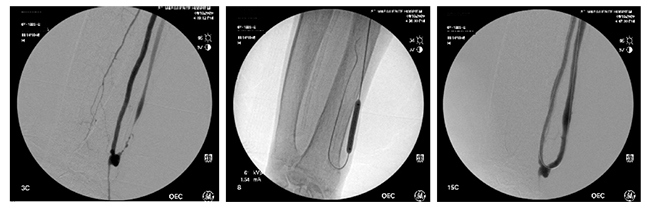

シャント造影検査

シャントとは、血液透析を行うため、腕の動脈・静脈をある部分でつなぎ合わせることです。血栓などで腕の血管が狭くなると血液透析に支障をきたします。

この場合もバルーン(風船)を膨らませることで血管を拡げます。透視で血管を観察しながらの検査・治療です。

術中外科用イメージ装置 GE社製 OEC9900 Elite standard-C9)

検査例